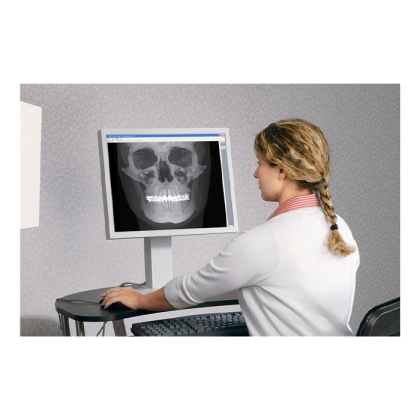

Аппарат гарантирует быструю реконструкцию снимков благодаря высокочувствительному датчику с размером рабочей области 20x25 см, поддерживающему форматы 2D и 3D. Переключение между режимами осуществляется одной кнопкой, не требуя дополнительных настроек или оборудования. Чувствительность датчика гарантирует отличное качество панорамных снимков и 3D моделей.

- Программное обеспечение для диагностики i-CatVision / eXamVision и 3DVR